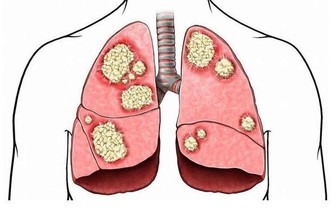

服藥3天后,譚先生覺得頭越來越重、疲乏無力、小便黃,眼睛和皮膚出現黃疸,後來去醫院一查肝功能,發現膽紅素飆升到1000多單位,被診斷為急性藥物性肝衰竭和急性腎衰竭。

經過2個月的人工肝、血液超濾及腎透析等治療,譚先生才保住性命。